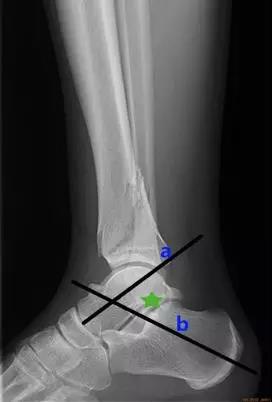

- 结节关节角:是在跟骨后关节面最高点与跟骨结节间做一连线,再在跟骨前端背侧最高点与后关节面最高点做另一连线,连线相交成角,称为结节关节(Böhler角)。

- 正常值:25°~40°

- 临床意义:跟骨结节关节角减小,提示跟骨骨折或扁平足;跟骨结节关节角增大,提示弓形足。